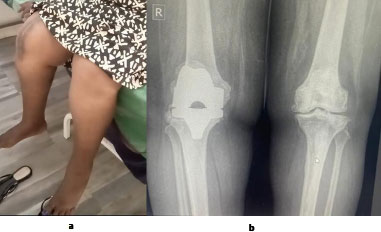

A 67-year-old patient at postoperative day 28 following right total knee arthroplasty. The patient demonstrates knee flexion greater than 110 degrees, full extension, and satisfactory correction of the right lower limb axis.